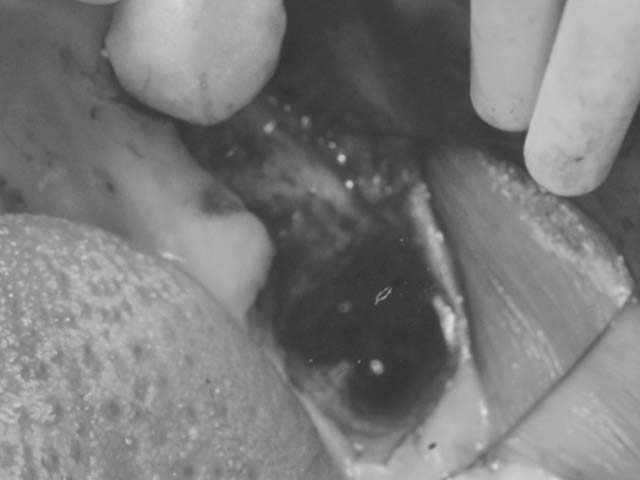

牙橋嚴重蛀牙,即拔即種,避免二次傷口 首頁 案例分享 人工植牙 牙橋嚴重蛀牙,即拔即種,避免二次傷口 多年前製作之牙橋,因為二度齲齒,導致支台齒蛀蝕,而需重新製作 牙橋支臺齒嚴重蛀牙 STEP1.拔除殘根並植入兩根植牙 STEP2.骨粉填補缺損骨頭缺陷 STEP3.三個月後,準備製作正式假牙 STEP4.正式假牙完成